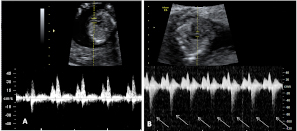

La ecografía en tres dimensiones muestra un feto de 13 semanas de gestación con el cordón umbilical alrededor del cuello. En la imagen rotatoria se puede observar la situación del cordón, que sube por el tórax y que seguramente puede causar complicaciones en el embarazo.